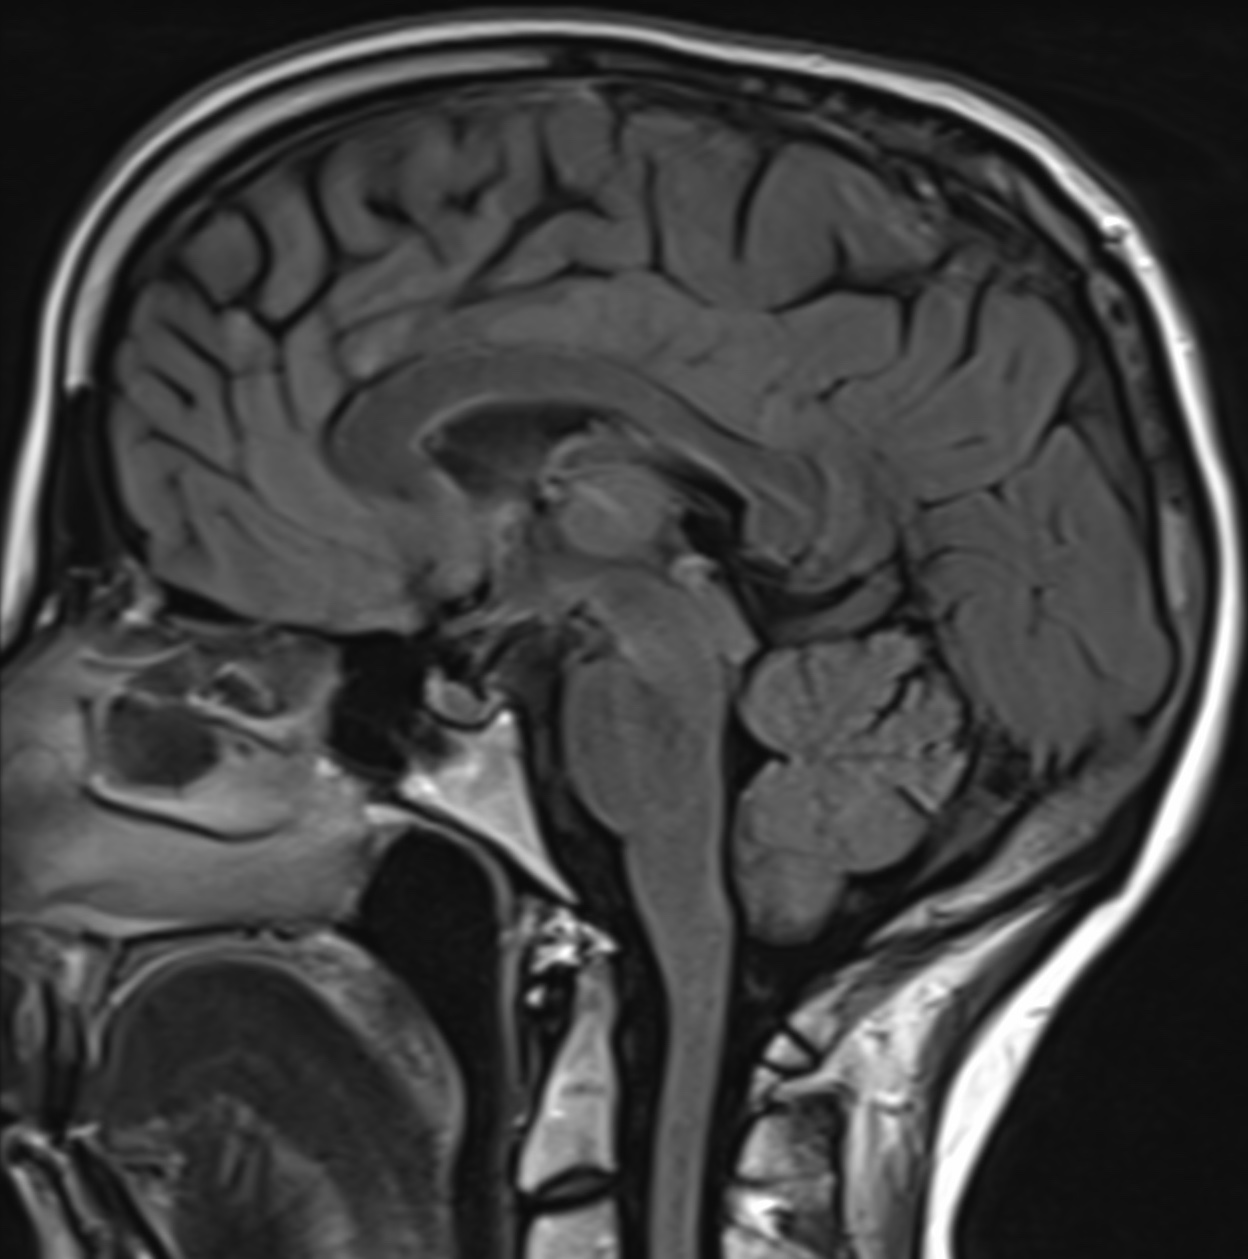

La durée de l’examen est variable selon la zone anatomique étudiée allant de 10 minutes (IRM cérébrale, IRM du genou, IRM d’épaule, IRM du poignet, IRM de la cheville, IRM cervicale, IRM lombaire …) à 25 minutes (IRM médullaire, IRM hépatique, IRM pancréatique, IRM rénale, IRM pelvienne, IRM de prostate…). Elle dépend également de la nécessité ou non d’injecter un produit de contraste (gadolinium).